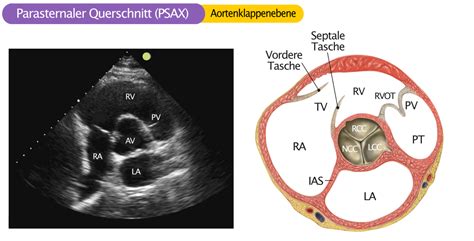

Aortenklappenstenose EKG & ECHO

Aortenklappenstenose EKG & ECHO from ekgecho.de